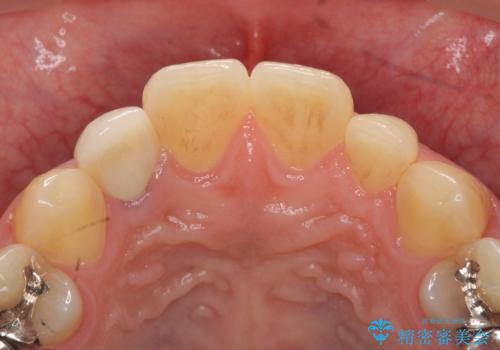

- 20代男性

- 金属を使っていない被せ物に替えたいといらっしゃった方の症例です。

再根管治療終了後、オールセラミッククラウンによる補綴を行いました。

今回用いたオールセラミッククラウンはジルコニアフレームという白い素材の上にセラミックを盛っているため、審美性が非常に高いのが特徴です。